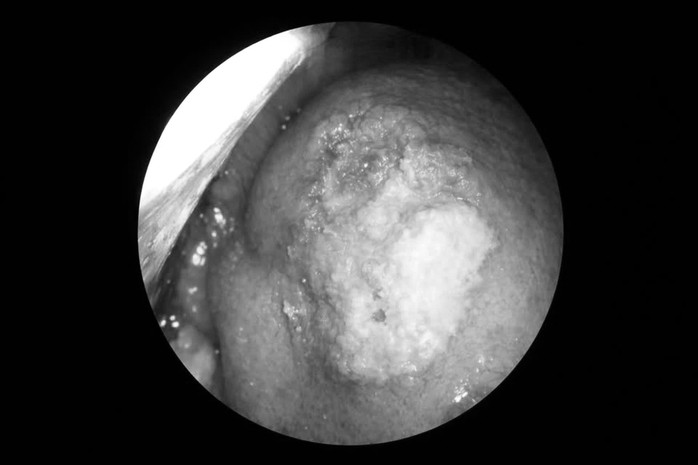

Tổn thương vùng lưỡi của bệnh nhân ung thư lưỡi

Tại Khoa Ung bướu, Bệnh viện Thanh Nhàn (Hà Nội), qua thăm khám, bác sĩ ghi nhận nhiều dấu hiệu nghi ngờ u ác tính và chỉ định sinh thiết lại. Kết quả xác định bệnh nhân mắc ung thư biểu mô vảy lưỡi - thể ung thư phổ biến nhất ở khoang miệng. Các xét nghiệm đánh giá giai đoạn gồm siêu âm và MRI, chưa ghi nhận di căn hạch cổ hay di căn xa.